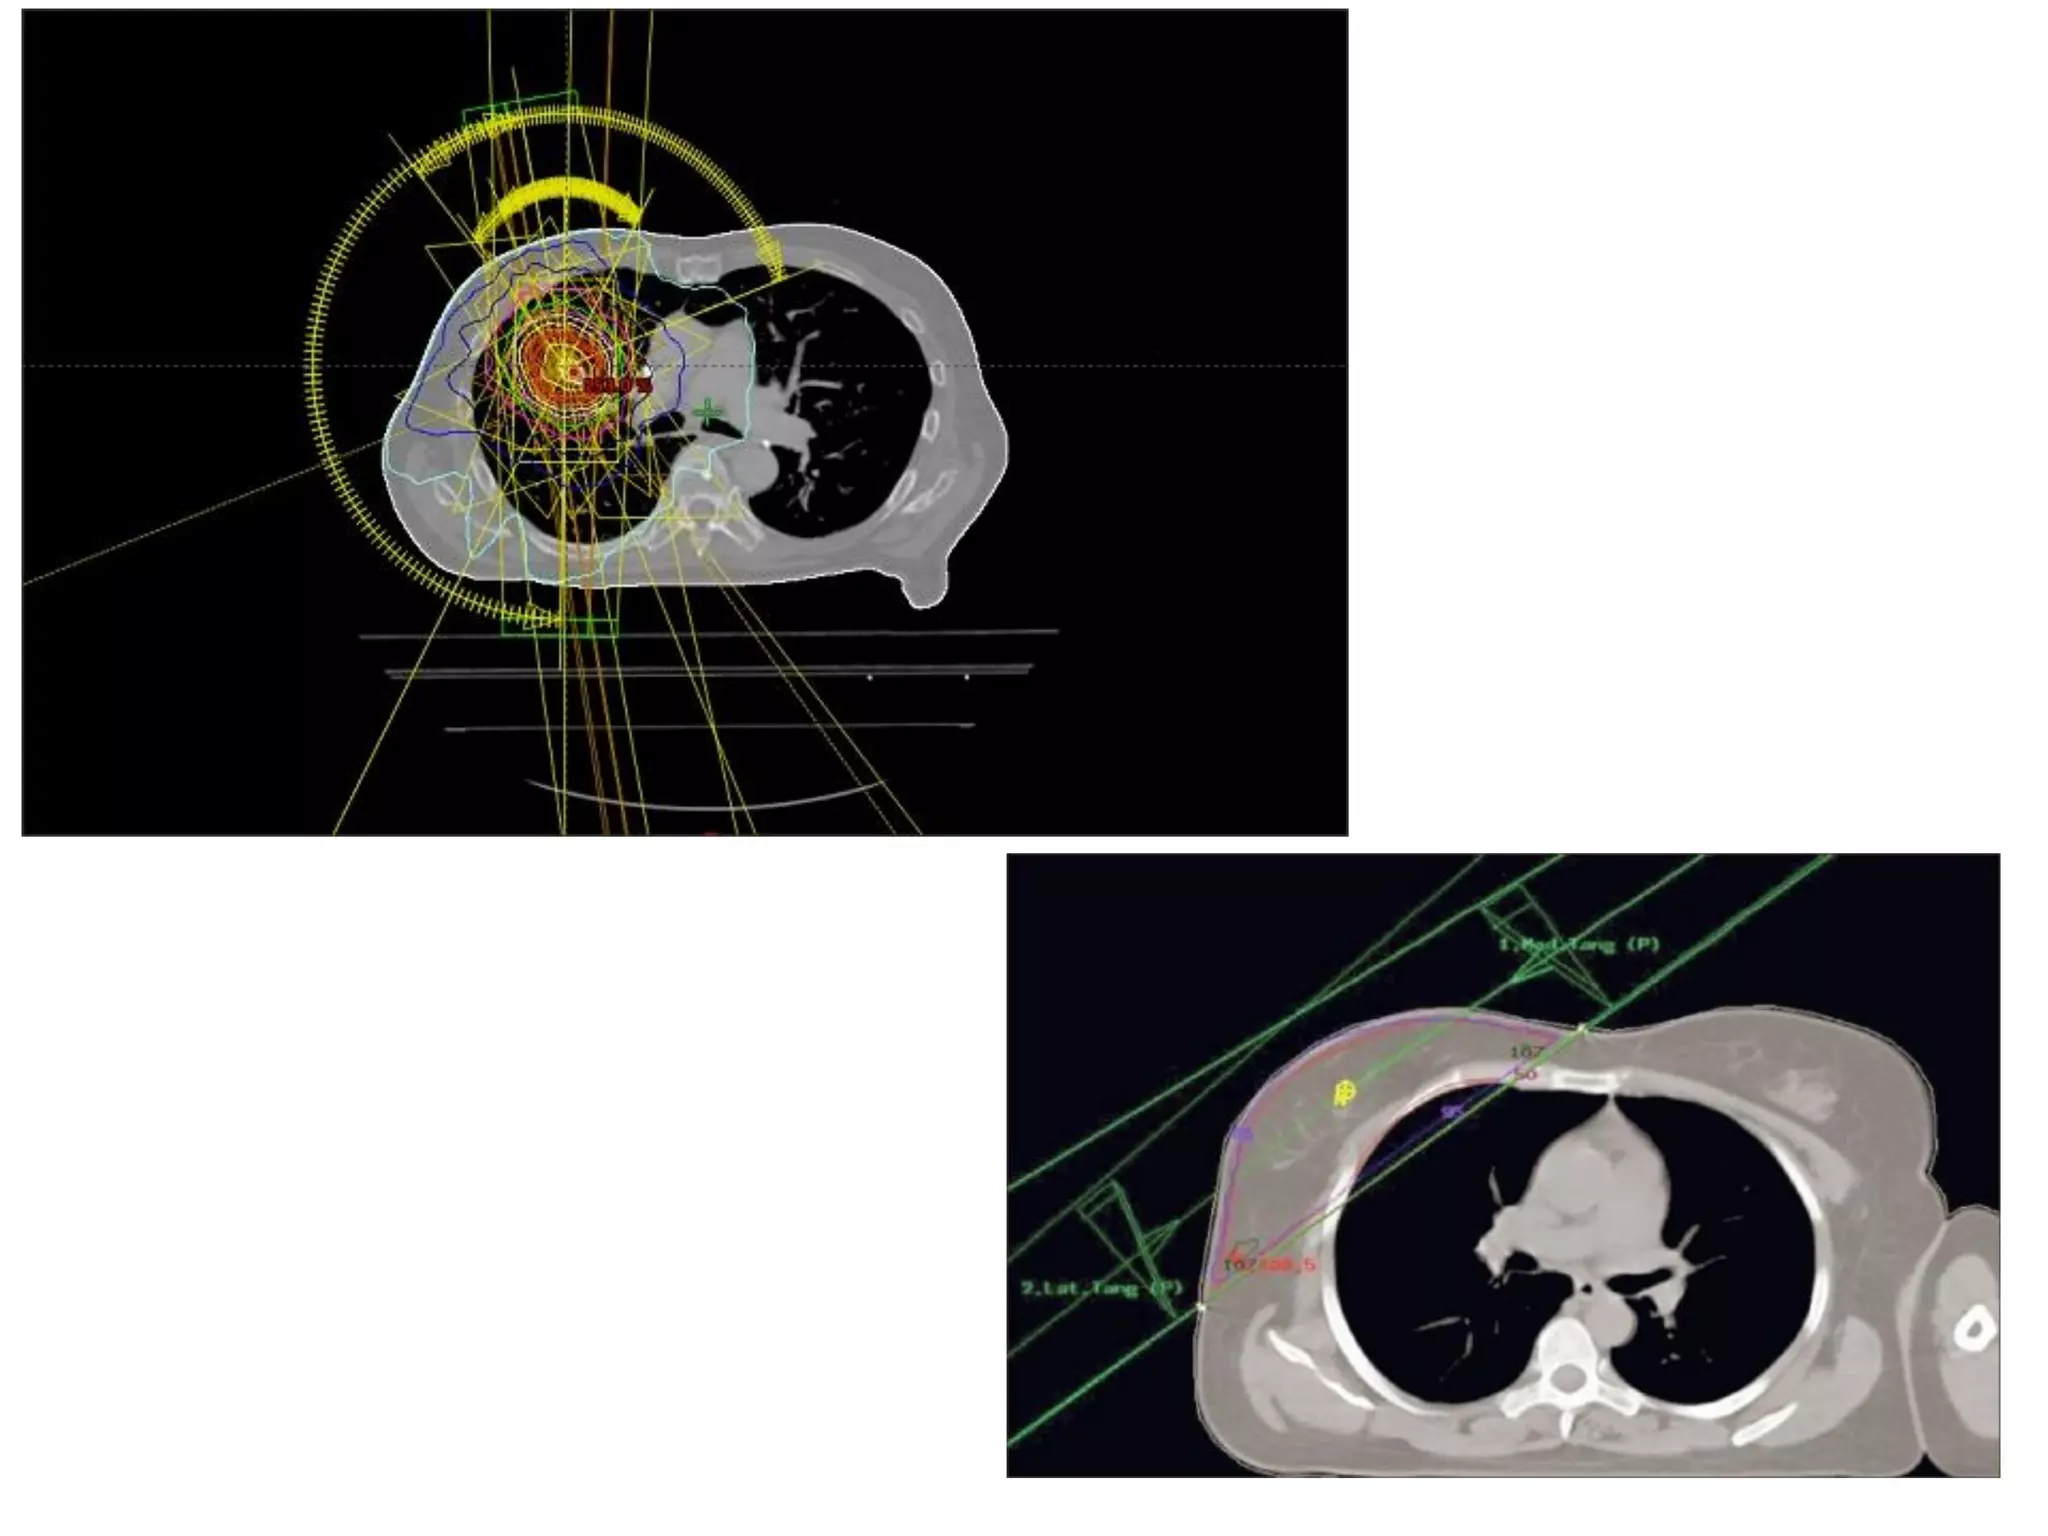

Treatment Planning

• The goal of treatment planning is to maximize

the radiation dose to the tumor while

minimizing the dose to organs at risk.

• The best treatment plan for each patient is

determined by a team consisting of radiation

oncologists, medical physicists, medical

dosimetrist, and radiation therapist, they plan

the appropriate external beam radiotherapy.

Treatment Planning • Thegoal of treatment planning is to maximize the radiation dose to the tumor while minimizing the dose to organs at risk. • The best treatment plan for each patient is determined by a team consisting of radiation oncologists, medical physicists, medical dosimetrist, and radiation therapist, they plan the appropriate external beam radiotherapy.